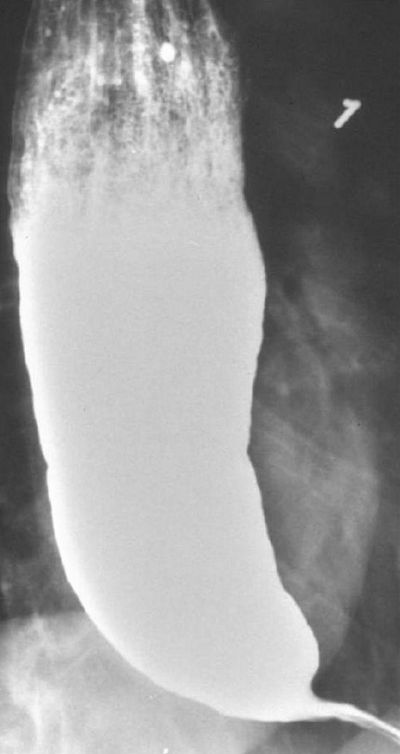

30-year-old male presents with a history of difficulty swallowing (dysphagia). It used to feel like solid foods got stuck in throat after swallowing, but since a week ago, it became difficult to swallow fluids too.

- Picture: Barium Swallow Study